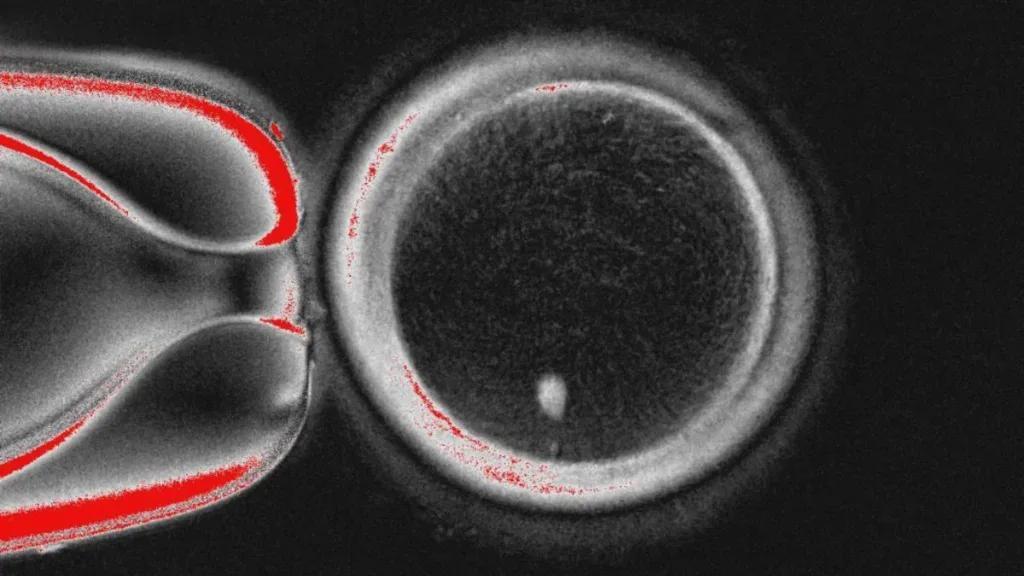

研究团队创新开发'有丝-减数分裂'(mitomeiosis)技术,通过电击刺激与roscovitine激酶抑制剂的'组合拳',成功诱导重组卵细胞完成减数分裂。这一过程精确排出23条染色体形成极体,最终生成染色体数量正常的'人造卵子'。该卵子与精子结合后,成功发育至囊胚阶段(6天)。